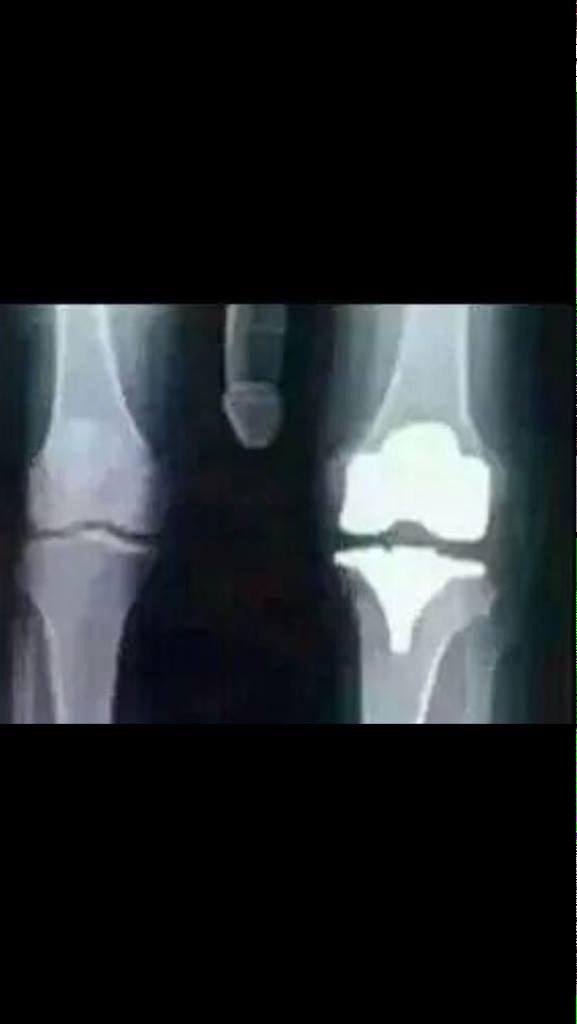

Happy Bday Todd Glass I hurt my Knee today picking up your present

I hurt my Knee today picking up your present